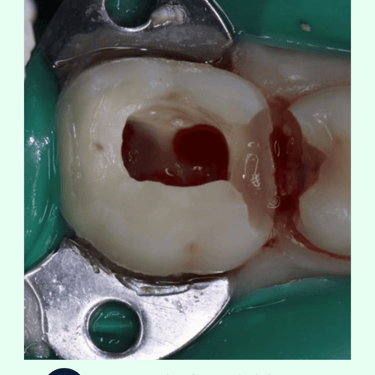

Apertura del Diente: Se realiza una pequeña apertura en la corona del diente para acceder a la cámara pulpar.

Desbridamiento y Drenaje: Se elimina la pulpa inflamada o infectada y se permite que el pus drene, aliviando la presión interna.

Sellado Temporal: Después del drenaje, la apertura se sella temporalmente hasta que se pueda realizar un tratamiento de conducto completo.